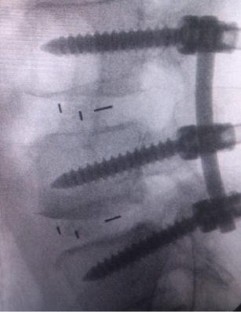

Fig. 3